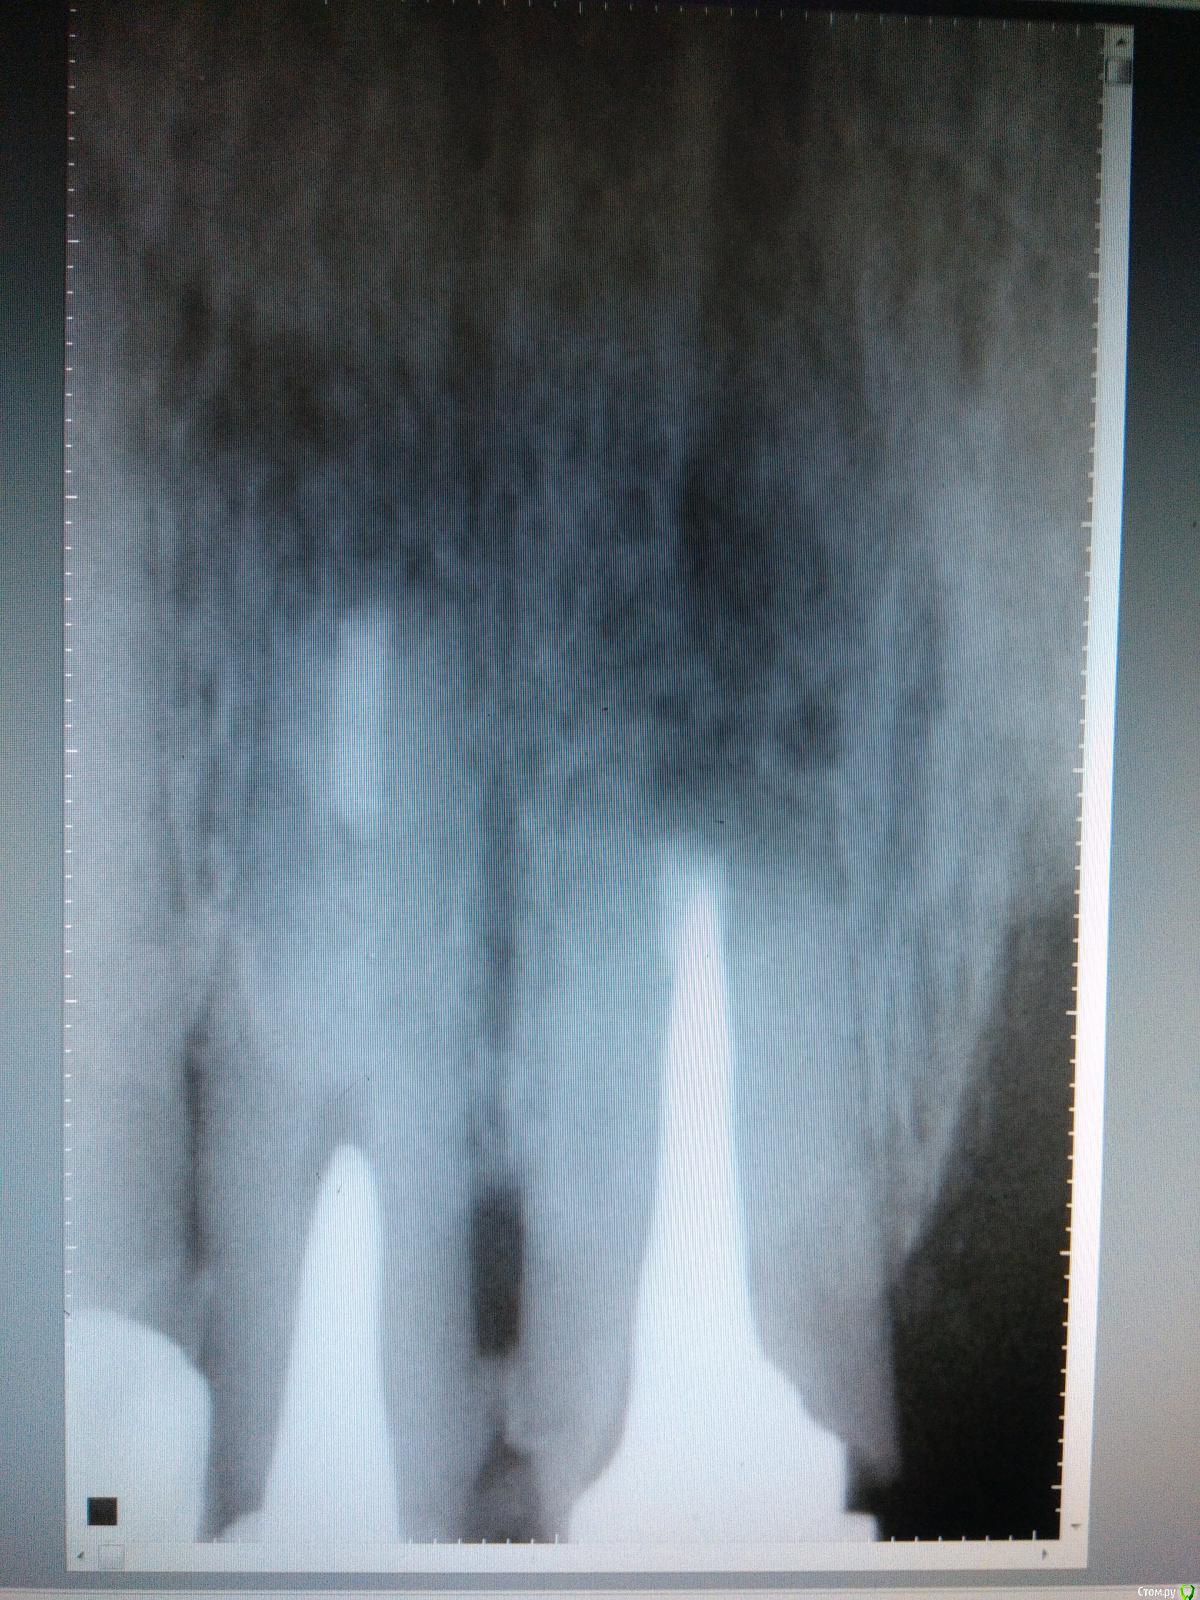

Kazankov.Egor Опубликовано 6 июля, 2018 Поделиться Опубликовано 6 июля, 2018 (изменено) Жалобы на неприятный запах изо рта, предположительно от 11 зуба. В анамнезе РВК 11 зуба.Скрины кт прилагаю. Пациент девушка, естественно, главный вопрос -эстетика. Нужна помощь по тактике. Изменено 6 июля, 2018 пользователем Kazankov.Egor Ссылка на комментарий

Kazankov.Egor Опубликовано 7 июля, 2018 Автор Поделиться Опубликовано 7 июля, 2018 Визуально, небольшая рецессия десны, кариес цемента. Ссылка на комментарий

Kazankov.Egor Опубликовано 7 августа, 2018 Автор Поделиться Опубликовано 7 августа, 2018 Какой максимальный срок наблюдения таких зубов? В инструкции пишут, что один год герметизм держит... irm использую Ссылка на комментарий

АнтонТЛТ Опубликовано 15 августа, 2018 Поделиться Опубликовано 15 августа, 2018 Почти 1,5 года. Сегодня на осмотр приходил 2 Ссылка на комментарий